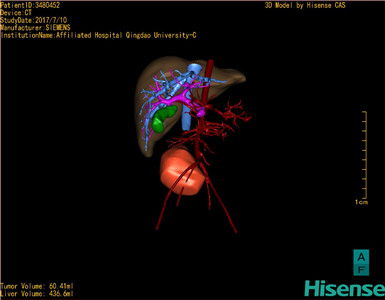

通过调节窗宽窗位调整CT序号,对肿瘤,肝实质,胆囊,下腔静脉,肿瘤,肝动脉、门静脉及肝静脉等进行三维重建;系统自动计算肿瘤体积和肝脏体积。模拟手术操作,自动计算切除肿瘤体积。肝脏体积为436.6ml,肿瘤体积为60.41ml,与血管联系紧密,术前手术方案的规划。

术前三维重建:

重建图片